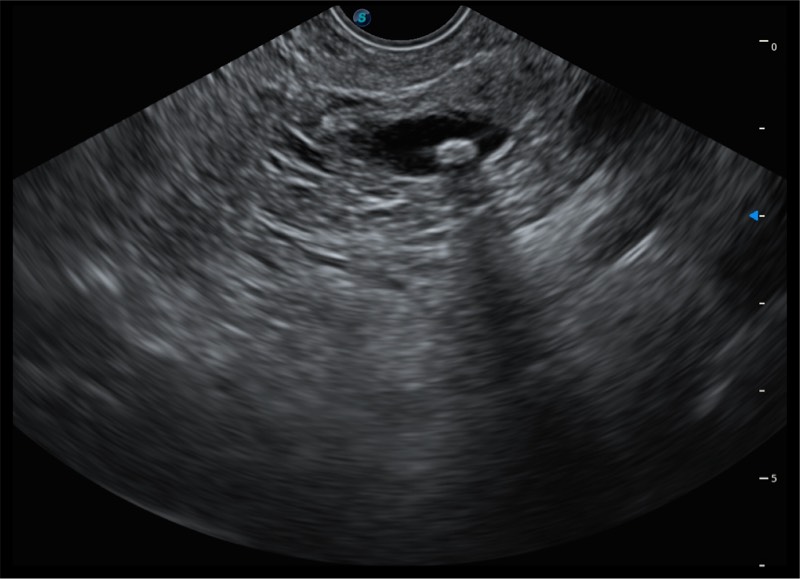

基于二十年的超声技术积累,乐玩lewin国际提供了最新一代的独立超声主机,在提供高质量图像的同时满足多学科使用。具备常见多普勒技术并提供弹性成像、声学造影等高端影像技术。新一代传感器具有更强的抗干扰能力并减少图像伪影。

150°超声扫描角度

4-12MHZ宽频输出